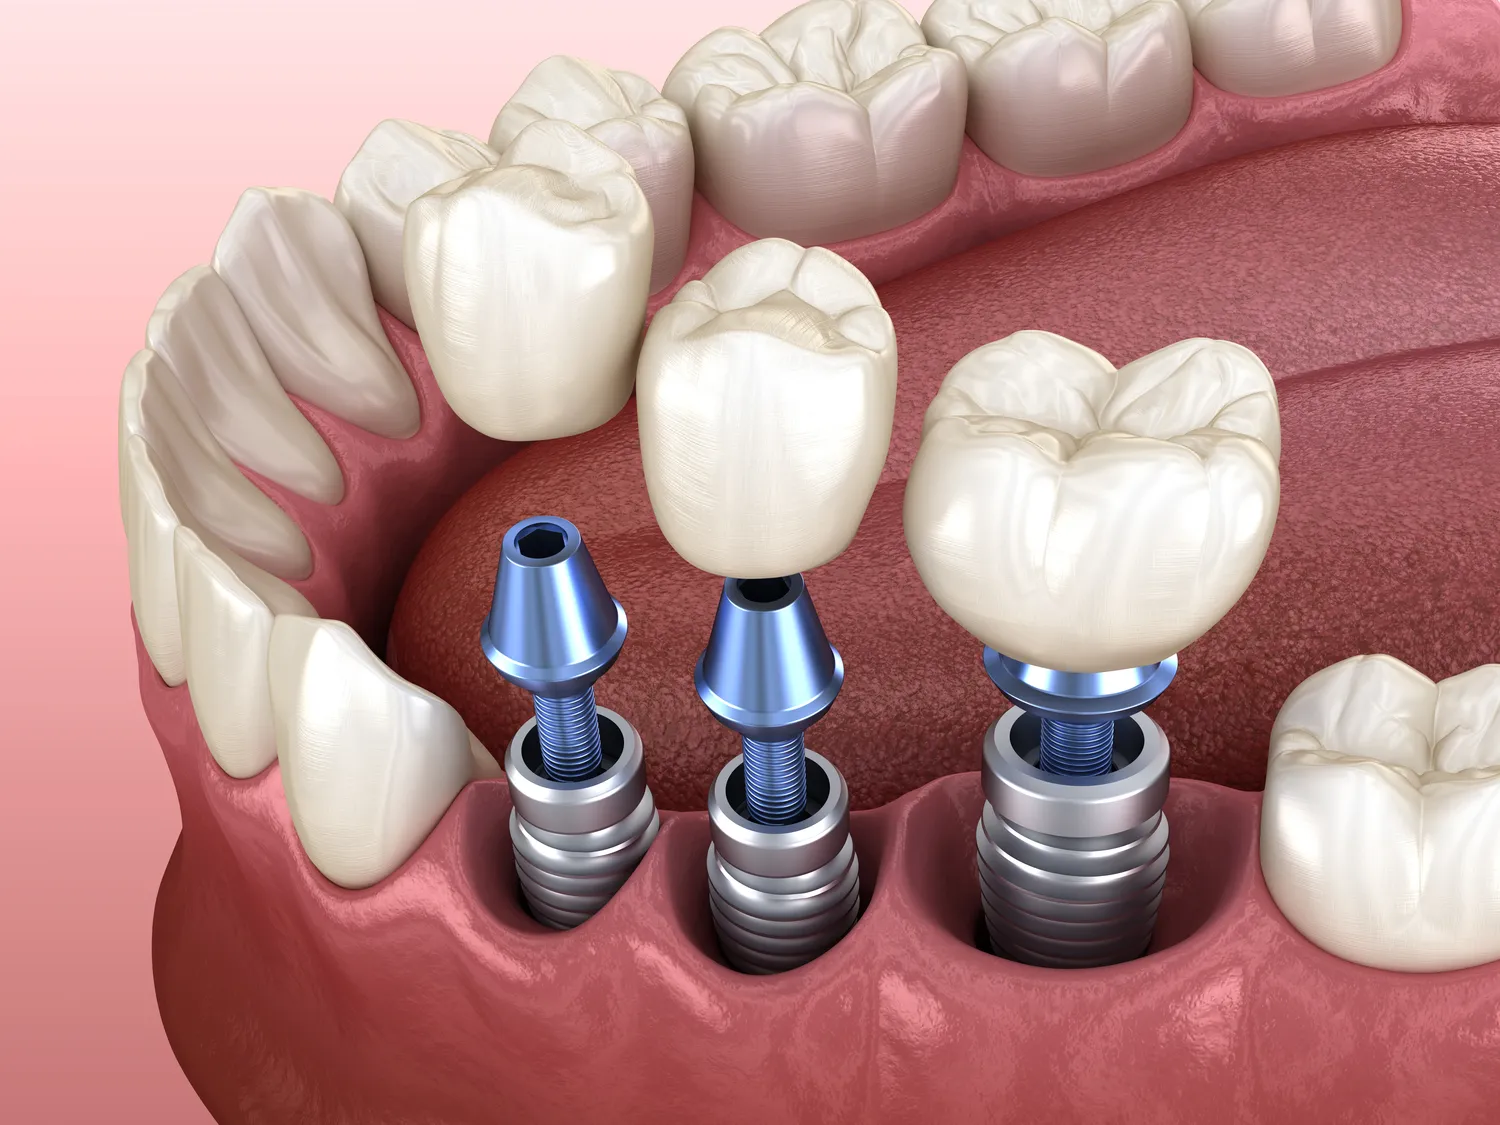

Wstawianie implantów dentystycznych to proces, który składa się z kilku kluczowych etapów, mających na celu zapewnienie trwałego i funkcjonalnego rozwiązania dla pacjenta. Pierwszym krokiem jest szczegółowa diagnostyka, która obejmuje zdjęcia rentgenowskie oraz badania tomograficzne, pozwalające lekarzowi ocenić stan kości oraz zaplanować odpowiednią lokalizację implantu. Następnie przeprowadza się zabieg chirurgiczny, podczas którego implant jest umieszczany w kości szczęki lub żuchwy. W trakcie tego etapu ważne jest, aby zachować jak najwyższe standardy aseptyki oraz techniki chirurgicznej, co minimalizuje ryzyko powikłań. Po wszczepieniu implantu następuje okres gojenia, który trwa zazwyczaj od kilku tygodni do kilku miesięcy, w zależności od indywidualnych predyspozycji pacjenta oraz jakości kości. W tym czasie implant integruje się z tkankami kostnymi, co jest kluczowe dla jego stabilności. Gdy proces gojenia dobiegnie końca, można przystąpić do kolejnego etapu, którym jest wykonanie korony protetycznej, która zostanie umocowana na implancie.

Czas gojenia po wszczepieniu implantu dentystycznego może różnić się znacznie w zależności od wielu czynników, takich jak stan zdrowia pacjenta, jakość kości oraz technika zastosowana podczas zabiegu. Zazwyczaj proces ten trwa od kilku tygodni do kilku miesięcy. Po pierwszym etapie wszczepienia implantu następuje faza osteointegracji, czyli procesu łączenia się implantu z tkanką kostną. Ten kluczowy etap może trwać od trzech do sześciu miesięcy; w przypadku pacjentów z dobrą jakością kości czas ten może być krótszy, natomiast u osób z problemami zdrowotnymi lub słabszą strukturą kostną może wydłużyć się nawet do dziewięciu miesięcy. Ważne jest również przestrzeganie zaleceń lekarza dotyczących diety oraz higieny jamy ustnej w tym okresie; unikanie twardych pokarmów oraz dokładne czyszczenie okolic implantu mogą przyspieszyć proces gojenia i zmniejszyć ryzyko powikłań. Po zakończeniu osteointegracji można przystąpić do wykonania korony protetycznej, co oznacza koniec procesu leczenia i możliwość cieszenia się nowym uśmiechem.